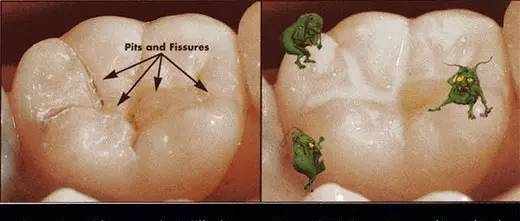

窝沟封闭

窝沟封闭又称点隙裂沟封闭(pit and fissure sealant),是指不去除咬合面牙体组织,在其上涂布一层粘结性树脂,保护牙釉质不受细菌及代谢产物侵蚀,增强牙齿抗龋能力,从而达到预防龋病发生的一种有效防龋方法。

1.为什么要进行窝沟封闭?

窝沟封闭最重要的作用就是可以避免发生龋齿。饮用水中的氟可以保护牙齿的光滑面,但后牙需要额外的保护。

窝沟封闭剂保护后牙咬合面上的细小窝沟,把食物和细菌隔绝在外。在牙齿龋坏以前给牙齿涂上封闭剂就能有效避免龋坏,从而大大地为患者节约了治疗时间和金钱。

而且,再看看牙齿表面这些深深的“藏身之处”,细菌套路这么深,牙刷也无力把它清扫干净啊。